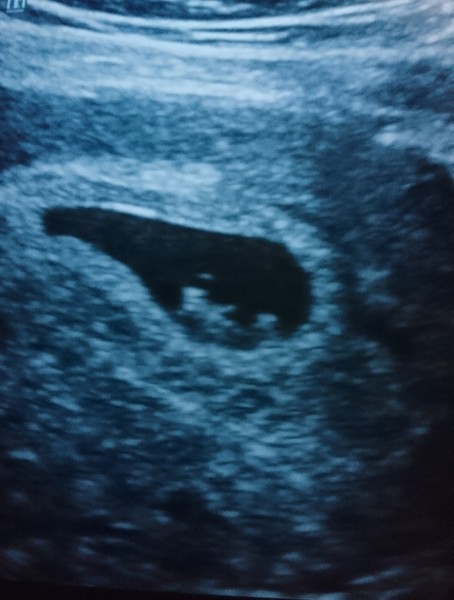

Sunshinesaz86 · 02/09/2017 17:31

We have 9 weeks exactly here EDD 7/4/18. So relieved 😌

Congrats to you oli and why x x

Babies due in April 2018